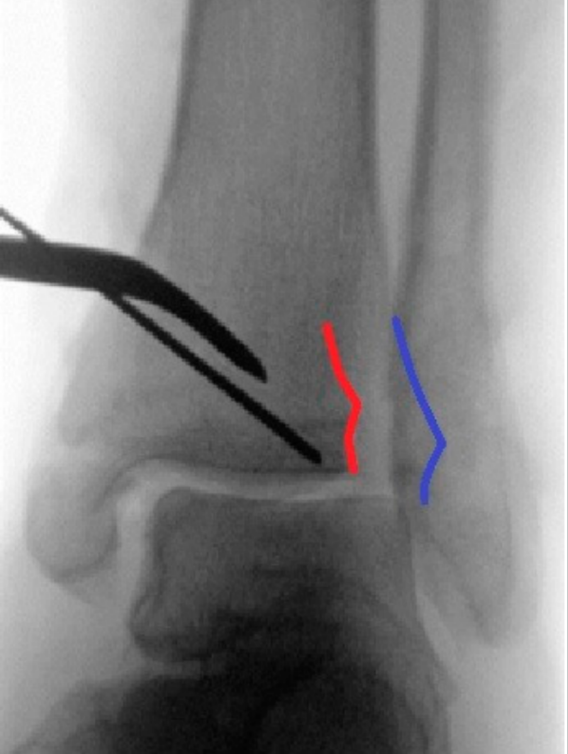

仔细行骨膜下剥离后,显露后踝骨折,清除嵌入的软组织,使用尖头复位钳进行解剖复位并临时固定(图3a)。确认复位满意后,于胫骨平台外侧三分之一、骨骺瘢痕近端确定导针进针点。此位置允许建立垂直于骨折平面的由后向前螺钉轨迹,从而在**化加压的同时避免关节内穿入。

经一长约1厘米的纵向皮肤切口,显露胫骨前侧皮质。在透视引导下,并使用两把小号Longbeck拉钩保护伸肌腱及神经血管结构,将一枚用于4.5毫米无头双螺纹加压螺钉的1.6毫米导针,从前内侧向后外侧、以约5-10°的向远端倾斜角置入(图3b–d)。经术中三维透视确认导针位置正确后(图3e),测量所需螺钉长度。

图3. (a–e): (a) 使用尖头复位钳临时固定;(b) 从前向后置入1.6毫米导针;(c) 踝穴位片,红线标记腓骨切迹后缘,蓝线标记前缘;(d) 点状末端视图证实轨迹位于切迹外;(e) 术中三维透视显示导针正确走行。